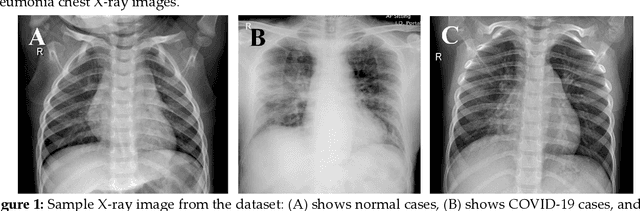

Abstract:Coronavirus disease (COVID-19) is a pandemic disease, which has already infected around 3 million people and caused fatalities of above 200 thousand. The aim of this paper is to automatically detect COVID-19 pneumonia patients using digital x-ray images while maximizing the accuracy in detection using image pre-processing and deep-learning techniques. A public database was created by the authors using three public databases and by collecting images from recently published articles. The database contains a mixture of 190 COVID-19, 1345 viral pneumonia, and 1341 normal chest x-ray images. An image augmented training set was created with around 2600 images of each category for training and validating four different pre-trained deep Convolutional Neural Networks (CNNs). These networks were tested for the classification of two different schemes (normal and COVID-19 pneumonia; normal, viral and COVID-19 pneumonia). The classification accuracy, sensitivity, specificity and precision for both the schemes were 98.3%, 96.7%, 100%, 100% and 98.3%, 96.7%, 99%, 100%, respectively. The high accuracy of this computer-aided diagnostic tool can significantly improve the speed and accuracy of diagnosing cases with COVID-19. This would be highly useful in this pandemic where disease burden and need for preventive measures are at odds with available resources.